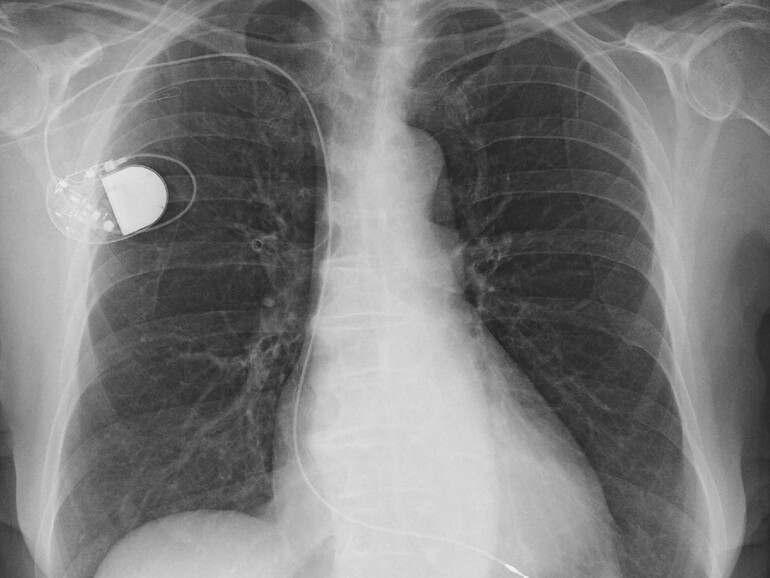

Wer beispielsweise einen Herzschrittmacher oder ein anderes medizinisches Gerät implantiert bekommen hat, sollte das iPhone 12 und seine Verwandten, aber auch das MagSafe-Zubehör mit einem kleinen Sicherheitsabstand verwenden. Apple schreibt von etwa 30 cm.

Das bedeutet, dass die Apple-Geräte beispielsweise im Fall von Herzschrittmachern nicht gerade in der Hemdbrusttasche oder der Jackeninnentasche getragen werden sollten. Bei anderen medizinischen Geräten wie Insulinpumpen, die an anderen Stellen sitzen, gilt natürlich, den Abstand dazu zu wahren.

Apple schreibt: „Medizinische Geräte wie implantierte Herzschrittmacher und Defibrillatoren können Sensoren enthalten, die bei engem Kontakt auf Magnete und Funkquellen reagieren. Um mögliche Wechselwirkungen mit diesen Geräten zu vermeiden, sollten Sie Ihr iPhone und MagSafe-Zubehör in einem sicheren Abstand zu Ihrem Gerät aufbewahren (mehr als 15 cm auseinander oder mehr als 30 cm auseinander, wenn Sie kabellos laden).“ Apple verweist auch auf die Hinweise von Geräteherstellern, die Implantatträger berücksichtigen sollen. Das Ganze gilt natürlich nicht für passive Implantate ohne Elektronik etwa künstliche Hüftgelenke.

Im Heart Rhythm Journal wurde vor kurzem darauf hingewiesen, dass Apples iPhone 12-Modelle aufgrund von magnetischen Interferenzen mit implantierten medizinischen Geräten Probleme verursachen könnten.